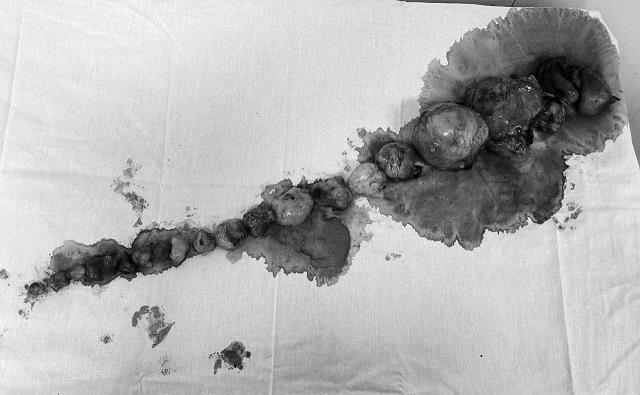

В Казани врачи РКБ удалили сразу 20 миом 39-летней жительнице Алькеевского района Татарстана, у которой девять лет назад уже удаляли шесть миоматозных узлов.

Медики пояснили, что со временем узлы снова выросли, добавилась еще и киста. Во время обследований специалисты даже говорили, что на фоне такого количества миом практически не видно матку, и, скорее всего, ее придется удалить.

Однако специалисты отделения гинекологии РКБ Татарстана сдаваться просто так не захотели. Около двух с половиной часов три акушера-гинеколога вырезали узлы с шеечным и перешеечным расположением.

В результате, команде РКБ удалось сохранить матку и избавить пациентку от множества образований. Врачи отметили, что женщина уже вернулась домой, чувствует себя отлично — избавилась от болей в пояснице, которые беспокоили ее в последнее время.